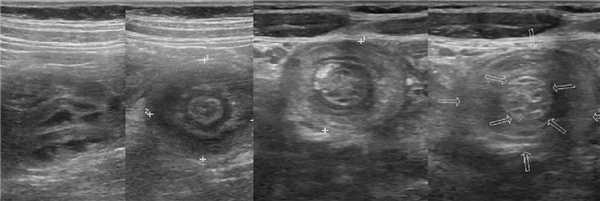

Кишечный инвагинат на УЗИ

Рисунок. Кишечный инвагинат на продольном и поперечном срезах УЗИ: влагалище инвагината (А) — тонкий гипоэхогенный поясок снаружи, следом дубль висцеральной брюшины (MS) — едва заметная гиперэхогенная полоска, отечный внешний (В) и внутренний (С) цилиндры тела инвагината — гипоэхогенные кольца, которые перемежает дубль висцеральной брюшины (S) и брыжейка (М). На уровне головки инвагината (1) разделяющая полоска тонкая. По направлению к основанию инвагината из-за брыжейки разделяющая полоска становится шире, приобретает форму полумесяца (2) и даже может включать лимфоузлы (3).

Рисунок. Кишечный инвагинат имеет слоистое строение. На продольных срезах УЗИ видно «вилы» (1) или «сэндвич» (2) — три гипо- и две гиперэхогенные полосы. Внешние гипоэхогенные полосы — влагалище и наружный цилиндр тела инвагината; внутренняя гипоэхогенная полоса — внутренний цилиндр тела инвагинат; гиперэхогенные полосы — дубль висцеральной брюшины в «вилах» и брыжейка в «сэндвиче». Если брыжейка располагается только по одну сторону от внутреннего цилиндра инвагината, то на изображении «псевдопочка» (3).

Рисунок. На гистологических и УЗИ срезах можно разглядеть три кишечные петли с пятислойными стенками: вблизи головки инвагината (1); ближе к основанию инвагината (2); рядом с внутренним цилиндром попадаются лимфоузлы брыжейки (3).

Рисунок. Мальчик 7-ми лет поступил в больницу с резкой приступообразной болью в животе и рвотой. На УЗИ в брюшной полости определяется цилиндрическая слоистая масса — гипо- и гиперэхогенные структуры чередуются. На продольном срезе (1) хорошо видно влагалище и головку инвагината, которая покрыта гиперэхогенной «шапочкой» испражнений. На поперечных срезах (2, 3) четко прослеживается гипоэхогенные внешний и внутренний цилиндры тела инвагината, промеж них гиперхогенный жир брыжейки с гипоэхогенными «бусинами» лимфоузлов (3). Лимфоузлы брыжейки увеличены (4). Заключение: Эхо-признаки инвагинации кишечника. Мезаденит.